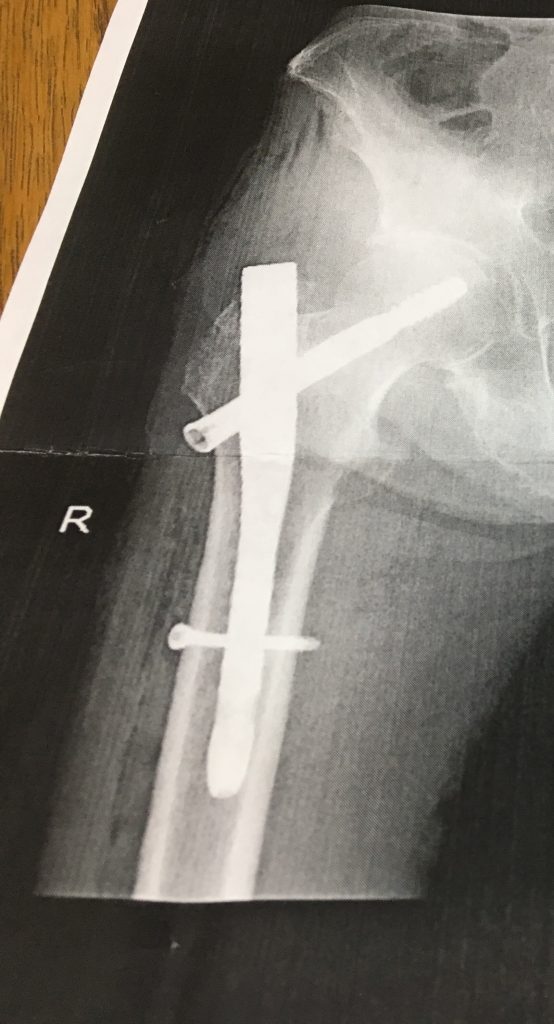

私事で恐縮ですが、

5月に大腿骨骨折をし手術をしました76歳の父も、予定より少し早い6月末に退院し、

現在は多少の可動域の低下はあるものの、すっかり元気に回復しました。